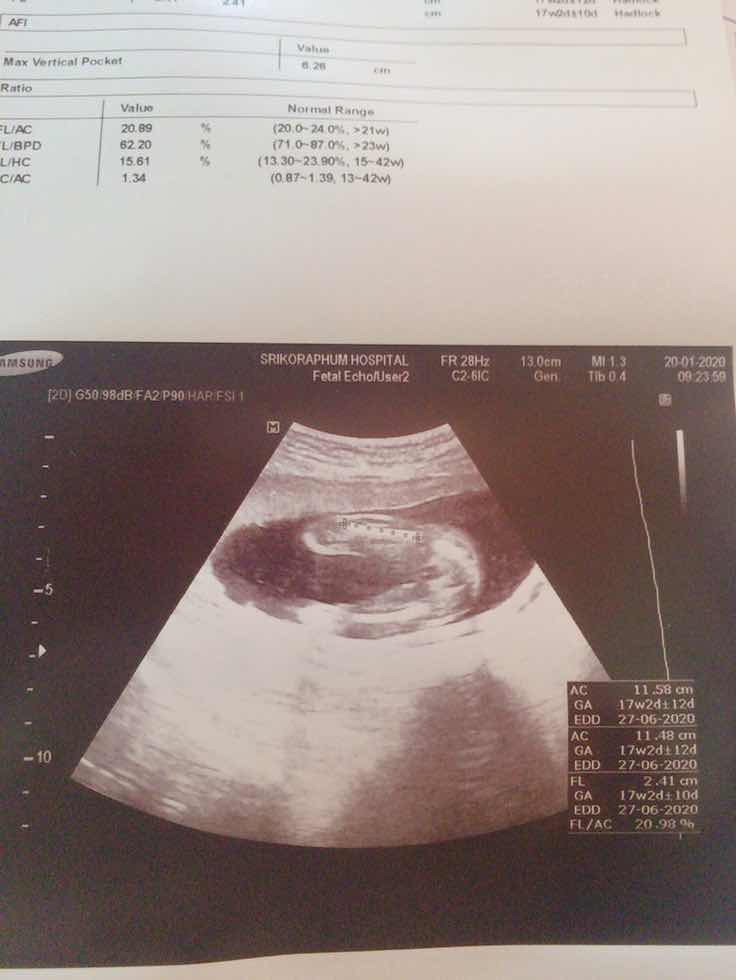

สอบถามหน่อยค้ะ

พอดีไปซาวดูเพศน้องหันหลังอยู่ตรงนี้คือขาน้องน้องหันทางก้นมาให้หมอบอกว่าตรงลูกศรบวกคือจิ๋มช่วยดูทีค่ะ

ผญ.เลยค่าาา เป็นแฮมเบอร์เกอร์รอยแยกชัด แต่ถ้าผช.จริงๆจะเป็นไข่กลมๆมีจุ้ดจู๋โผล่มาหน่อยๆ

ถ้าเป็นผู้ชายเห็นจู๋ชี้เลยคะ อันนี้น่าจะผู้หญิงนะคะ

น่าจะใช่ค่ะ ถ้าเป็นจู๋ต้องโด่ออกมาแล้วจ้า

จิ๋มค่ะแม่ ชัดมากกก อิๆ

น่าจะสามเหลี่ยมคะ ญ